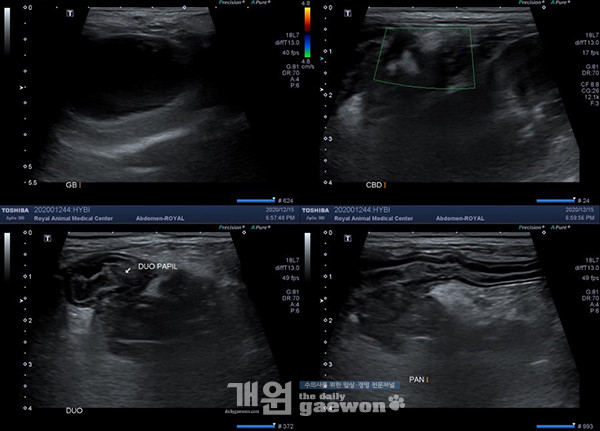

다음은 복부 초음파 사진입니다. 초음파 소견은 다음과 같습니다. 담낭의 심한 확장; 확장된 담낭 내 unechoic fluid 충만; 십이지장벽의 corrugation; 췌장 주변 지방의 심한 에코 상승; 췌장 주변 지방 조직 일부에서 unechoic cyst; duodenal papillae 개구부 주변 CBD의 확정 소견 관찰되지 않음; 담낭에서 십이지장까지 CBD의 추적이 어려우며, 주변 지방의 염증으로 인한 CBD의 허탈 상태 의심. GB dilation이 확진됩니다. 감별진단으로는 CBD obstruction(EHBO)/cholangitis, pancreatitis, duodenitis가 있습니다[그림 6].